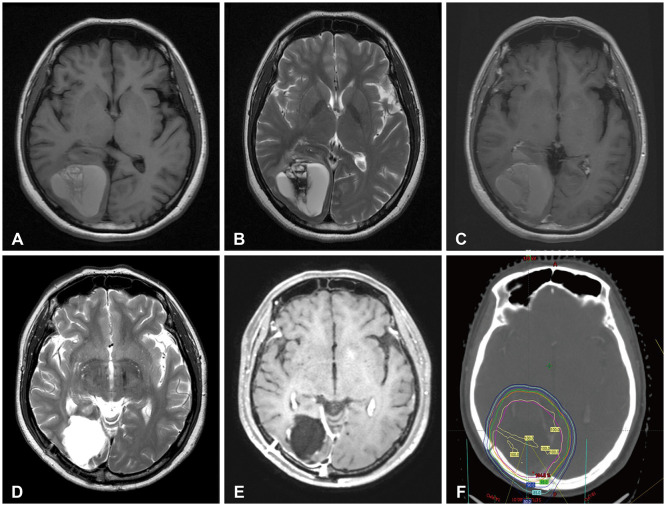

Delayed cerebral necrosis is a well-known complication of radiation therapy (RT). Because of its irreversible nature, it should be avoided if possible, but avoidance occurs at the expense of potentially compromised tumor control, despite the use of the modern advanced technique of conformal RT that minimizes radiation to normal brain tissue. Risk factors for radiation-induced cerebral necrosis include a higher dose per fraction, larger treatment volume, higher cumulative dose, and shorter time interval (for re-irradiation). The same principle can be applied to proton beam therapy (PBT) to avoid delayed cerebral necrosis. However, conversion of PBT radiation energy into conventional RT is still short of clinical support, compared to conventional RT. Herein, we describe two patients with excessively delayed cerebral necrosis after PBT, in whom follow-up MRI showed no RT-induced changes prior to 3 years after treatment. One patient developed radiation necrosis at 4 years after PBT to the resection cavity of an astroblastoma, and the other developed brainstem necrosis that became symptomatic 6 months after its first appearance on the 3-year follow-up brain MRI. We also discuss possible differences between radiation changes after PBT versus conventional RT.